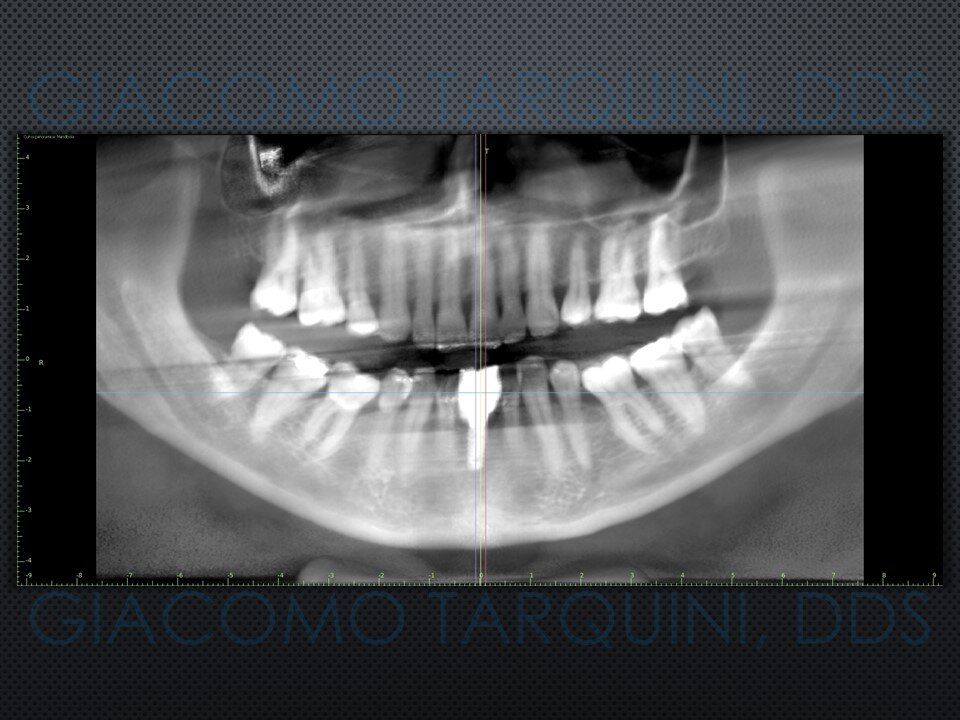

- Sondaggio e valutazione radiografica peri-implantare

- Rientro chirurgico e follow-up radiografico per valutare il grado di rigenerazione ossea ottenuta

CASO CLINICO: